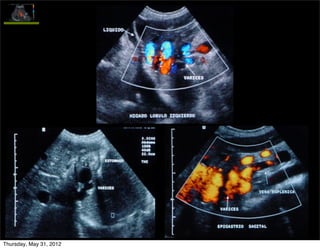

HP: circulación colateral y derivaciones

Permeabilidad vena paraumbilical

• Colateral portosistémica (caput medusae)

• Porta izquierda  v.paraumbilical  v.pared abdominal

Importancia de su dx: 1. podría prevenir la aparición

de VE, PERO 2. riesgo EH